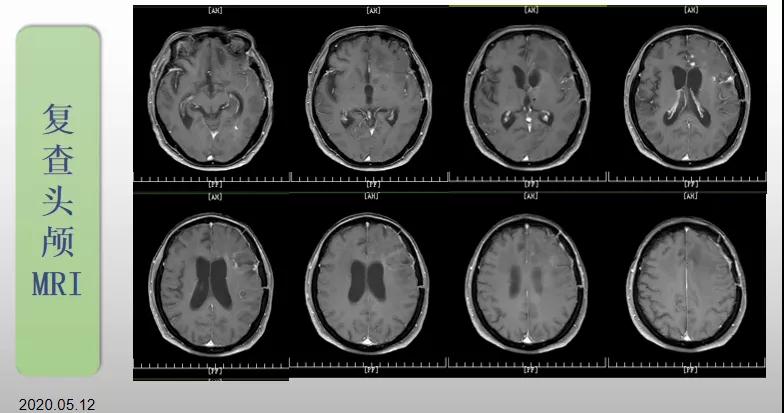

綜合治療 電場(chǎng)治療助70歲患者回歸正常生活

70歲的郝女士去年曾在外院查出“左額島葉”膠質(zhì)母細(xì)胞瘤(WHO Ⅳ級(jí)),并做了左側(cè)額島葉占位性病變切除術(shù)。術(shù)后進(jìn)行了同步放化療。由于治療條件有限,郝女士慕名來(lái)到我院就診。賀世明主任率領(lǐng)醫(yī)護(hù)團(tuán)隊(duì)立即為郝女士進(jìn)行了全面的檢查,決定為其進(jìn)行綜合治療 電場(chǎng)治療。經(jīng)過(guò)三個(gè)多月的綜合治療,患者復(fù)查頭顱MRI病變較前明顯縮小。出院時(shí),郝女士神志清醒,睡眠飲食正常,說(shuō)話很流利?!拔沂翘芍M(jìn)來(lái)的,現(xiàn)在不用人攙扶,自己就可以走出病房了?!焙屡坷t(yī)護(hù)人員的手說(shuō)。